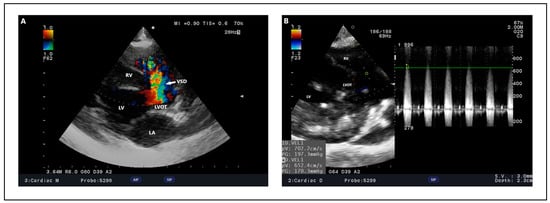

| [156] | Maltese and poodle mix | 5 | V/VI systolic right sided murmur, mild precordial thrill, jugular vein distension, nonproductive cough | Muscular, 5 | 1.1 m/s in systole, 0.9 m/s diastole | Transcatheter occlusion | Right ventricle enlargement with interventricular septal flattening, LVIDd/RVIDd < 1, MPA/AO ratio 1.41, RPA/AO ratio 0.72, PR 4.3 m/s (>74 mmHg), Qp:Qs—2.75 | LVIDd/RVIDd ratio 2.1, Ao/MPA ratio 0.81 Ao/RPA ratio 0.6 PR 1.84 m/s (13.5 mmHg), Qp:Qs ratio 1.3 | Enlargement of right cardiac silhouette (VHS 11.6), dilation of the main pulmonary artery and pulmonary vessels CVC/VL 1.8 | Sinus tachycardia (180–200 bpm), Deep S-wave | Clinically normal 9 months after procedure |

4.2. Echocardiography, Radiography, ECG Findings